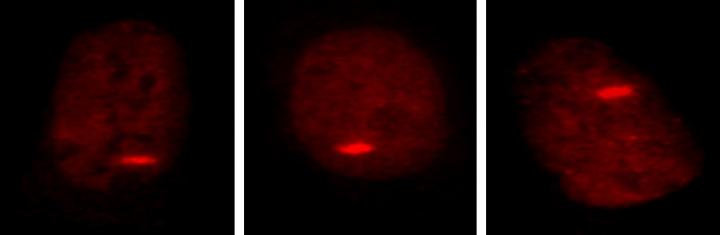

然后,这个研究组使用一个激光束导致结肠癌细胞系的DNA损伤。CHD4和它的修理队蛋白质再一次扑向了受损部位。

“这个结果提示,CHD4及其伴随蛋白质的存在可能是修复DNA损伤的一个通用系统的一部分,” Baylin说。他说,当这个研究组通过遗传干扰这个基因从而制止细胞制造CHD4,在暴露于过氧化氢或激光之后,伴随它的蛋白质就没有出现,这为这种理论增加了支持。